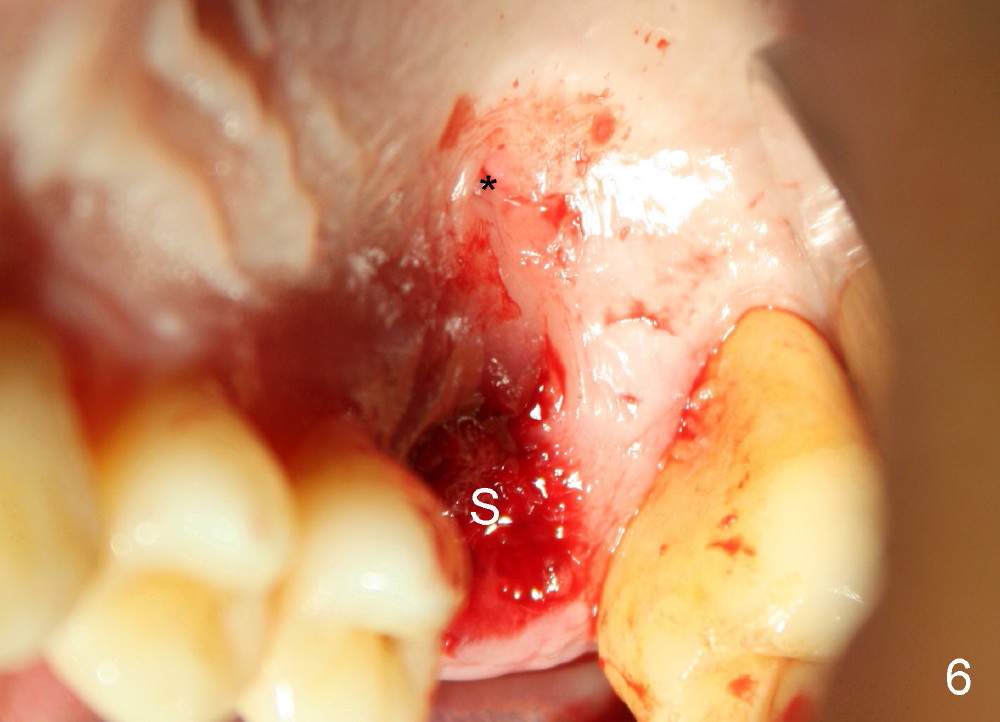

The upper right 1st molar of a 48-year-old man has severe perio endo disease (Fig.1 #3); the bone height for immediate implant (Fig.2) is about 3.5 mm (Fig.1 vertical line). There is a buccal (Fig.3 B) abscess (*); the palatal (Fig.4 P) root is exposed. After extraction, the socket available for immediate implant (Fig.5,6 S) is buccal (without septum), whereas the apex of the palatal root is far away from the main socket. In fact there is an advantage: the socket is smaller. Osteotomy is created in the main socket as palatal as possible, using osteotomes, reamers and taps (Fig.7 T). The sinus floor is lifted (Fig.7 ^). When 7x17 mm implant is placed (Fig.8 I), the insertion torque is >60 Ncm. The remaining socket (Fig.8 *) is to be packed with mixture of autogenous bone, allograft and synthetic bone (Osteogen) (Fig.9,10 <). Immediate insertion of an abutment (Fig.8-10 A) helps retain perio dressing (Fig.11,12). No collagen membrane is used in this case to cover the bone graft before placement of perio dressing. Postop the patient cannot tolerate oral Amoxicillin because of stomach upset. The dose is reduced. Two weeks postop, the perio dressing is stable, but discolors (Fig.13). When the dressing is removed, the buccal bone graft is exposed, which is not abnormal. What is unusual is discoloration (Fig.14). The significance of the latter is not revealed until 3 months postop when the patient remains asymptomatic, but there is an apical fistula (Fig.15 <). There is a communication between the fistula and the buccal sulcus of the implant: water passing freely. Based on the position of the buccal plate of the neighboring teeth (*), the buccal plate of the implant should be lost, which is consistent with finding of PA (Fig.16, as compared to Fig.8). Guided bone regeneration seems necessary.